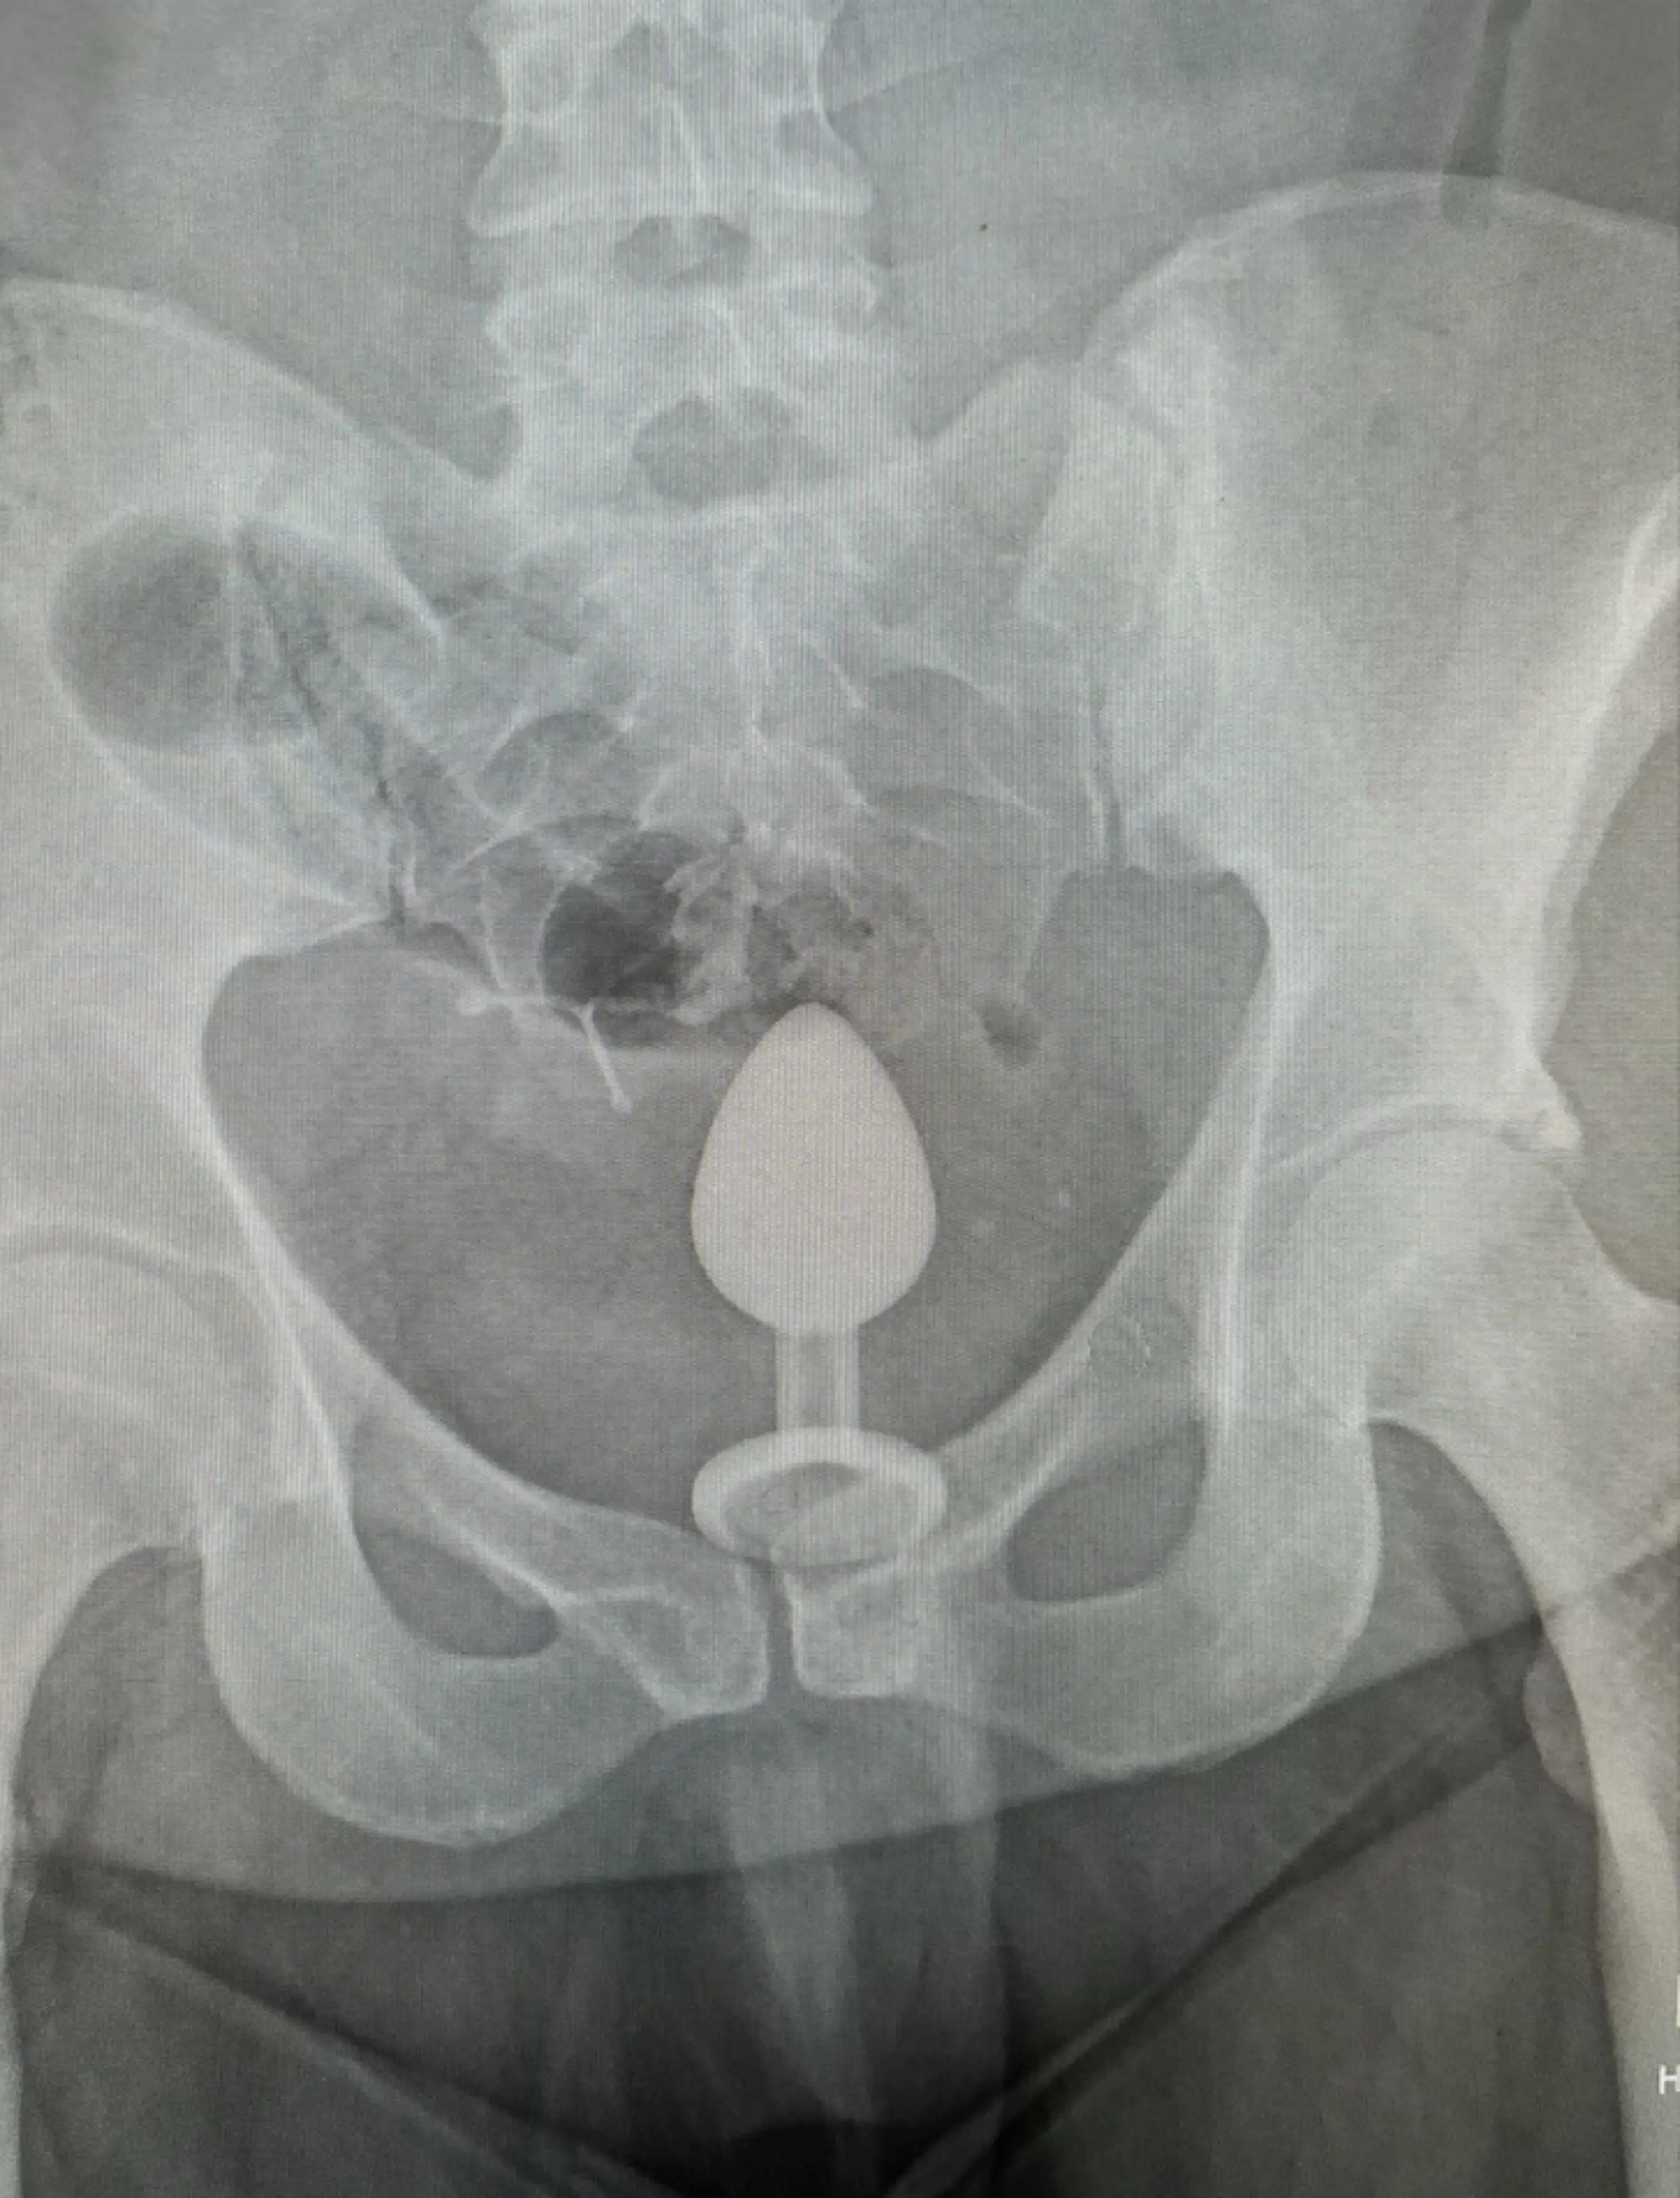

Luckily she got seen by a nurse after 10 minutes, though when doctors saw an x-ray of her predicament they 'didn't know how to get it out' and recommended that she go in for surgery.